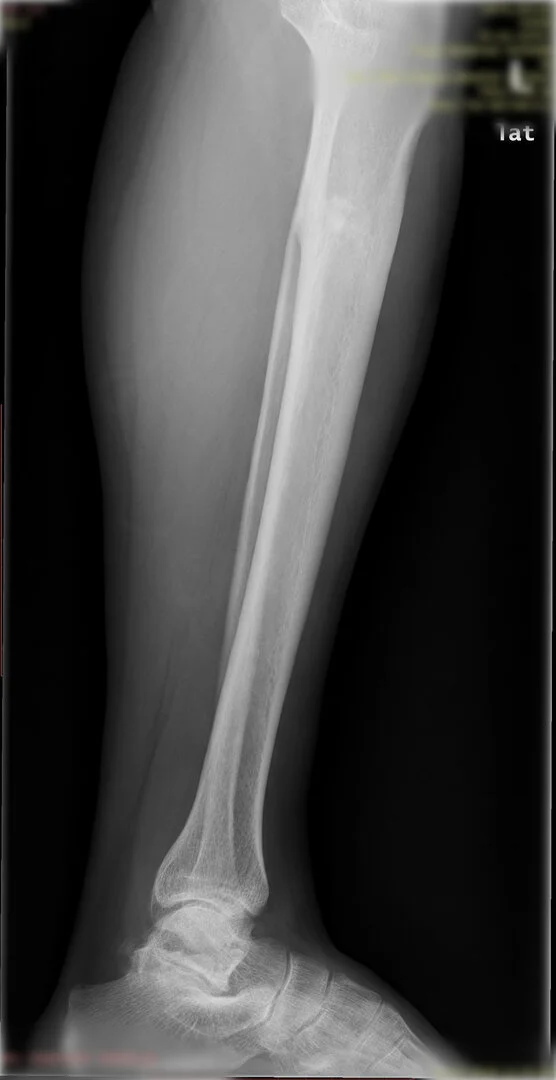

Deformite, bir kırık sonrası yanlış kaynama sonucunda olabileceği gibi doğumsal nedenlerden de olabilir.

Ameliyat öncesi deformitenin iyi analiz edilmesi, planlamanın ona göre yapılması gerekir. Deformite düzeltilmesi esnasında eğer kısalık var ise sıra ile iki problemin de aynı anda düzeltilmesi mümkündür.

Diğer bir yöntem akut olarak düzeltme yöntemidir. Bu yöntemde kemiğe uygulanılan tespit yöntemi plak-vida kombinasyonu olabileceği gibi bir intramedüller çivi de olabilir.

Hangi tespit yöntemini kullanacağınıza deformitenin yeri ve miktarına göre karar vermek gereklidir.

Görüntüleri büyütmek için üzerine tıklayınız.